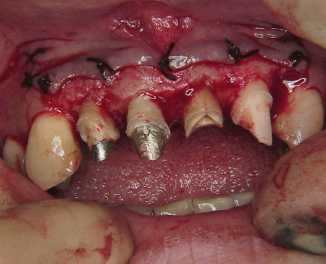

歯周手術